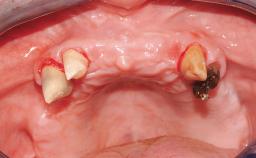

A healthy 31-year-old female patient presented with a failing maxillary left lateral incisor crown. The crown regularly loosened, and the remaining tooth was neither restorable nor rational to treat. The patient had a high smile line, a medium soft tissue biotype with a compromised mesial papilla (shorter than the contralateral one), and a horizontal scar in the buccal soft tissue as a result of past periapical surgery.

Timing of placement Immediate Placement (extraction sockets) (Type I)

Papilla Deficient

Recession Absent

Interproximal attachment At CEJ

Socket walls Intact

Thickness of buccal wall less than 2 mm

Anticipated residual defect after implant placement 2 mm or less